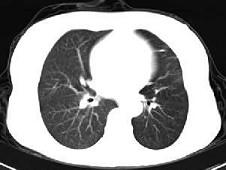

男,45岁,外伤后行CT检查如图,最可能的诊断为 ( )A、肺大疱B、支气管囊肿并感染C、左主支气管断裂D、畸胎瘤E、支气管肺炎

问题 男,45岁,外伤后行CT检查如图,最可能的诊断为 ( )

选项 A、肺大疱 B、支气管囊肿并感染 C、左主支气管断裂 D、畸胎瘤 E、支气管肺炎

答案 C